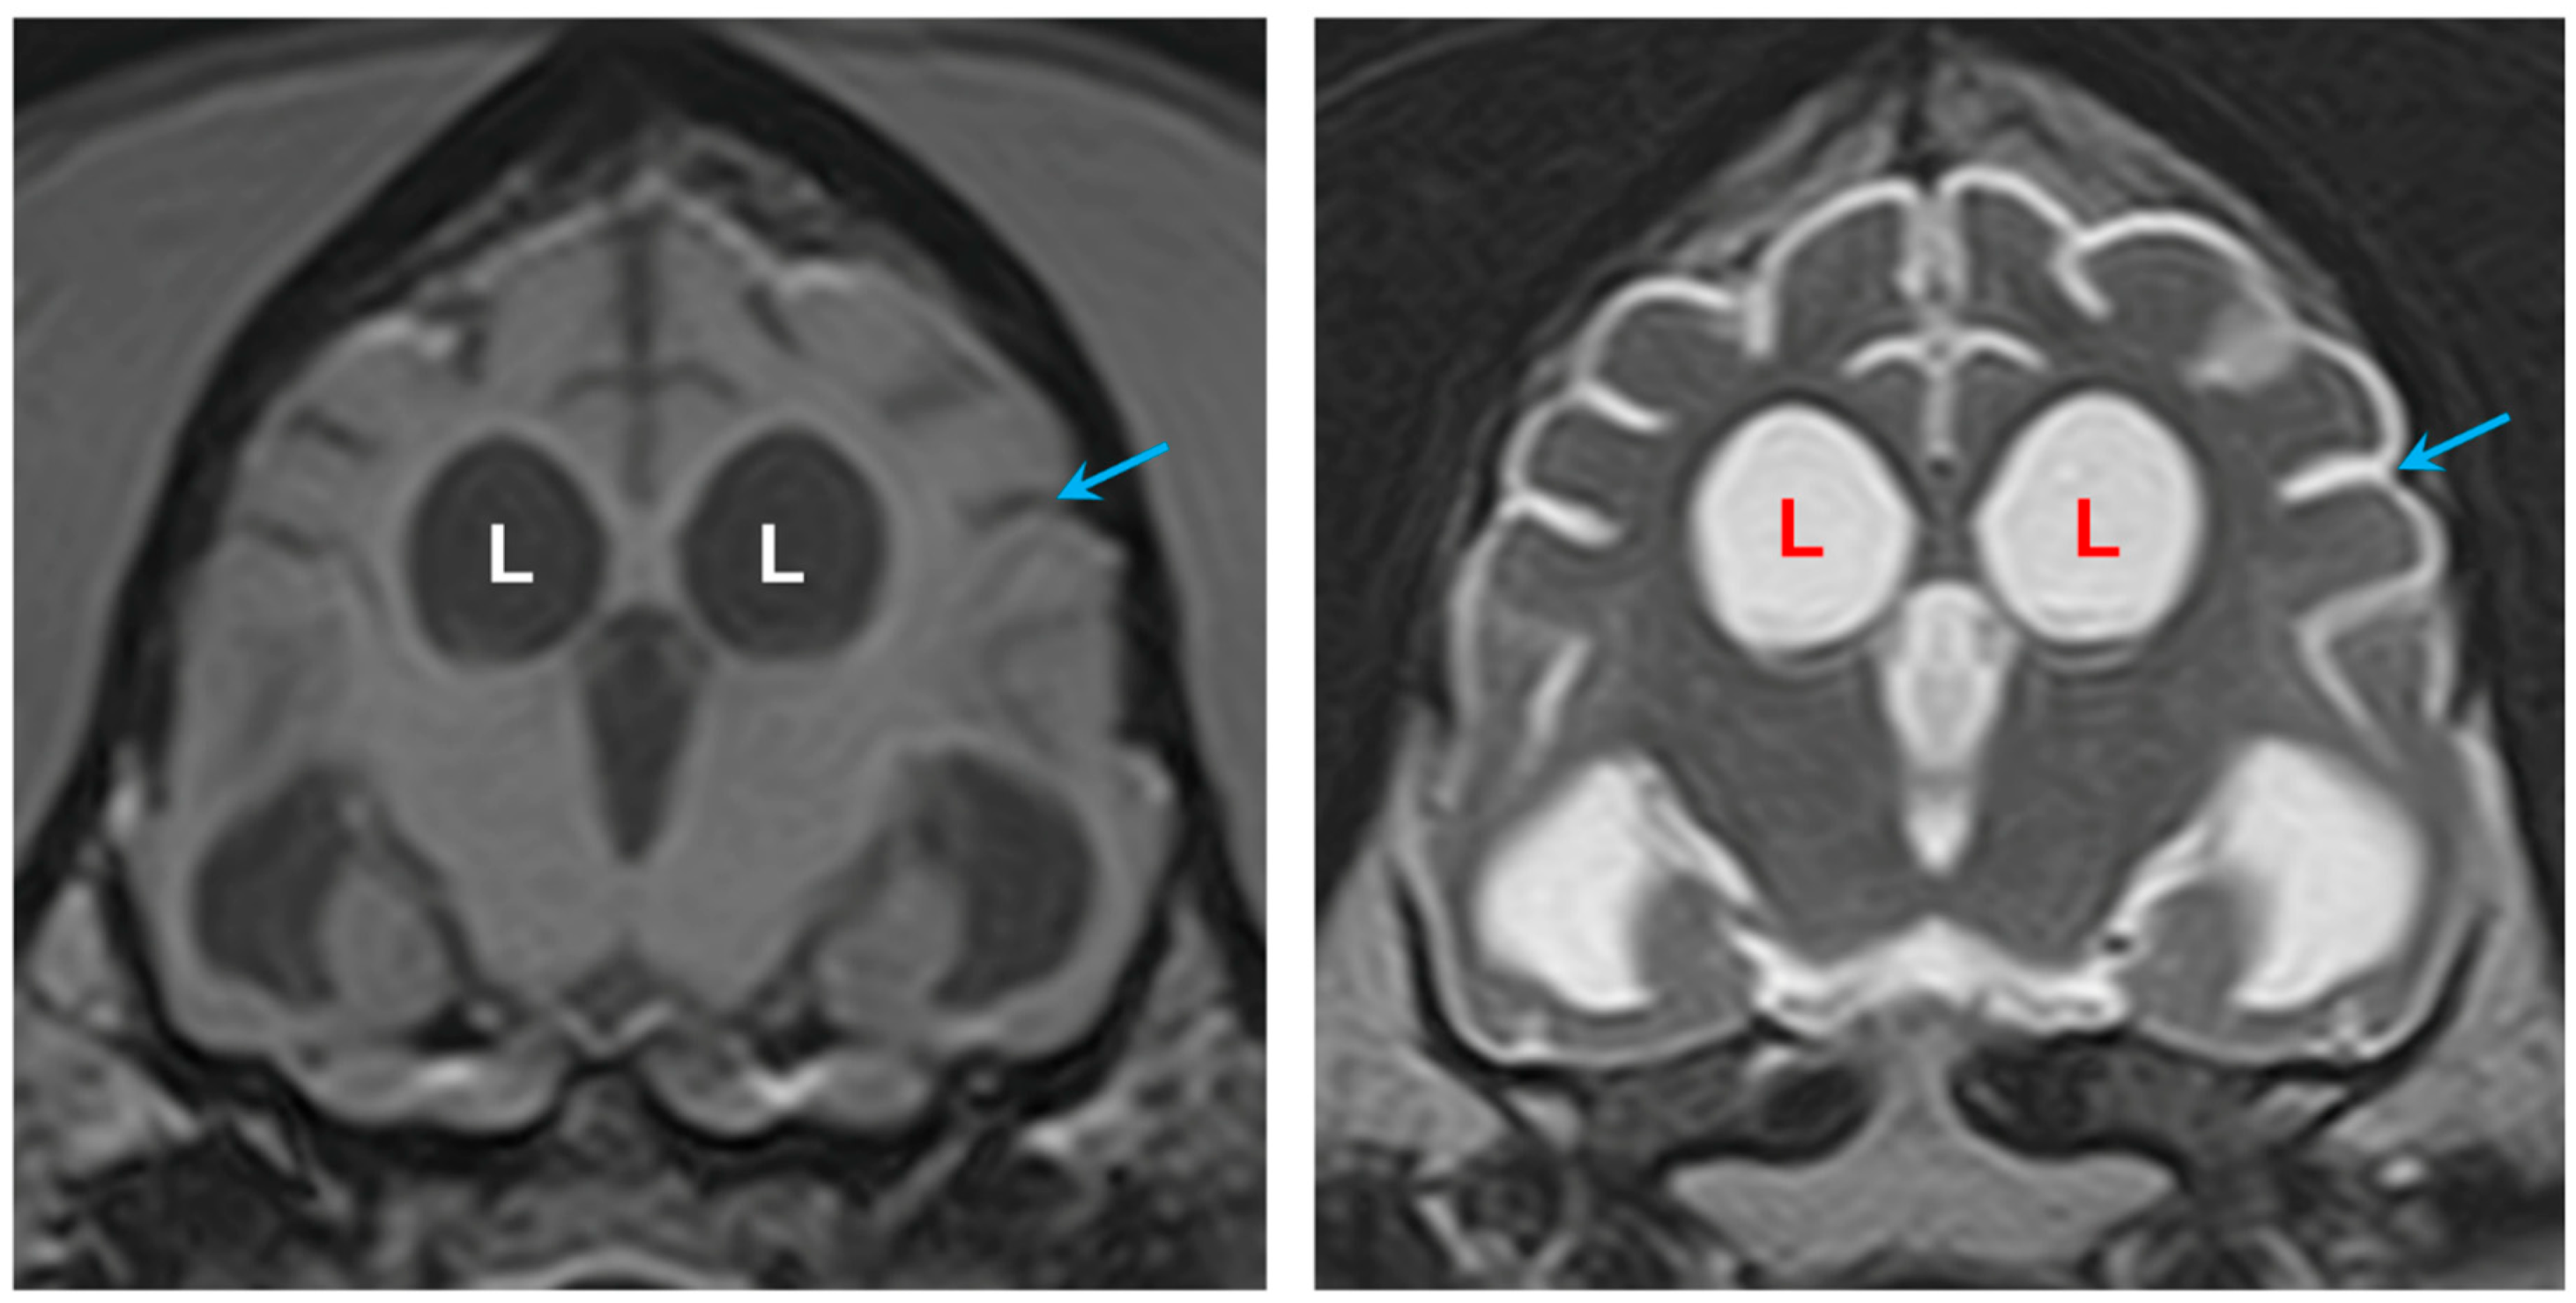

3.1. Disease Phenotype

3.2. Microscopic Findings